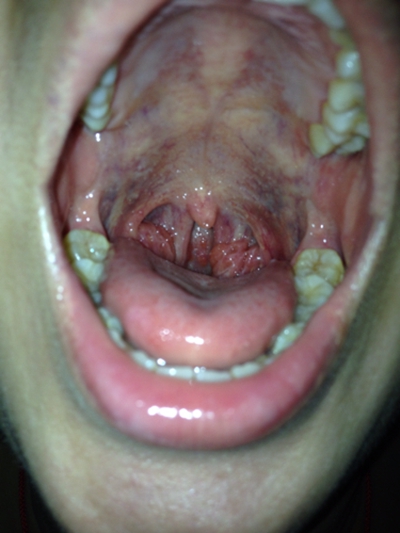

食道炎的症狀圖